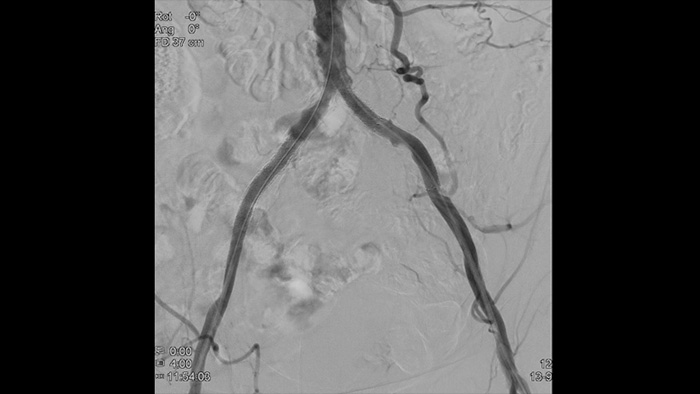

血管の高精細画像は血管の細部まで鮮やかに捉えるため、正確な治療戦略、ナビゲーション、フォローアップをサポートします。